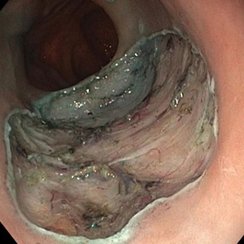

Eine Patientin stellte sich bei uns mit Beschwerden durch Gallensteine im Gallengang vor. Aufgrund der vorangegangenen Magenbypass-Operation war die Papille auf konventionellem endoskopischem Weg nicht erreichbar. Nach ausführlicher Aufklärung entschieden wir uns gemeinsam mit der Patientin für ein modernes, minimal-invasives Verfahren: die sogenannte EDGE-Prozedur (Endoscopic Ultrasound-Directed Transgastric ERCP).

Hierzu wurde zunächst mithilfe der Endosonographie (Ultraschall von innen) der ausgeschaltete Magenanteil aufgesucht. Dieser wurde gezielt punktiert und die korrekte Lage unter Röntgendurchleuchtung mit Kontrastmittel überprüft (Abbildung 1).